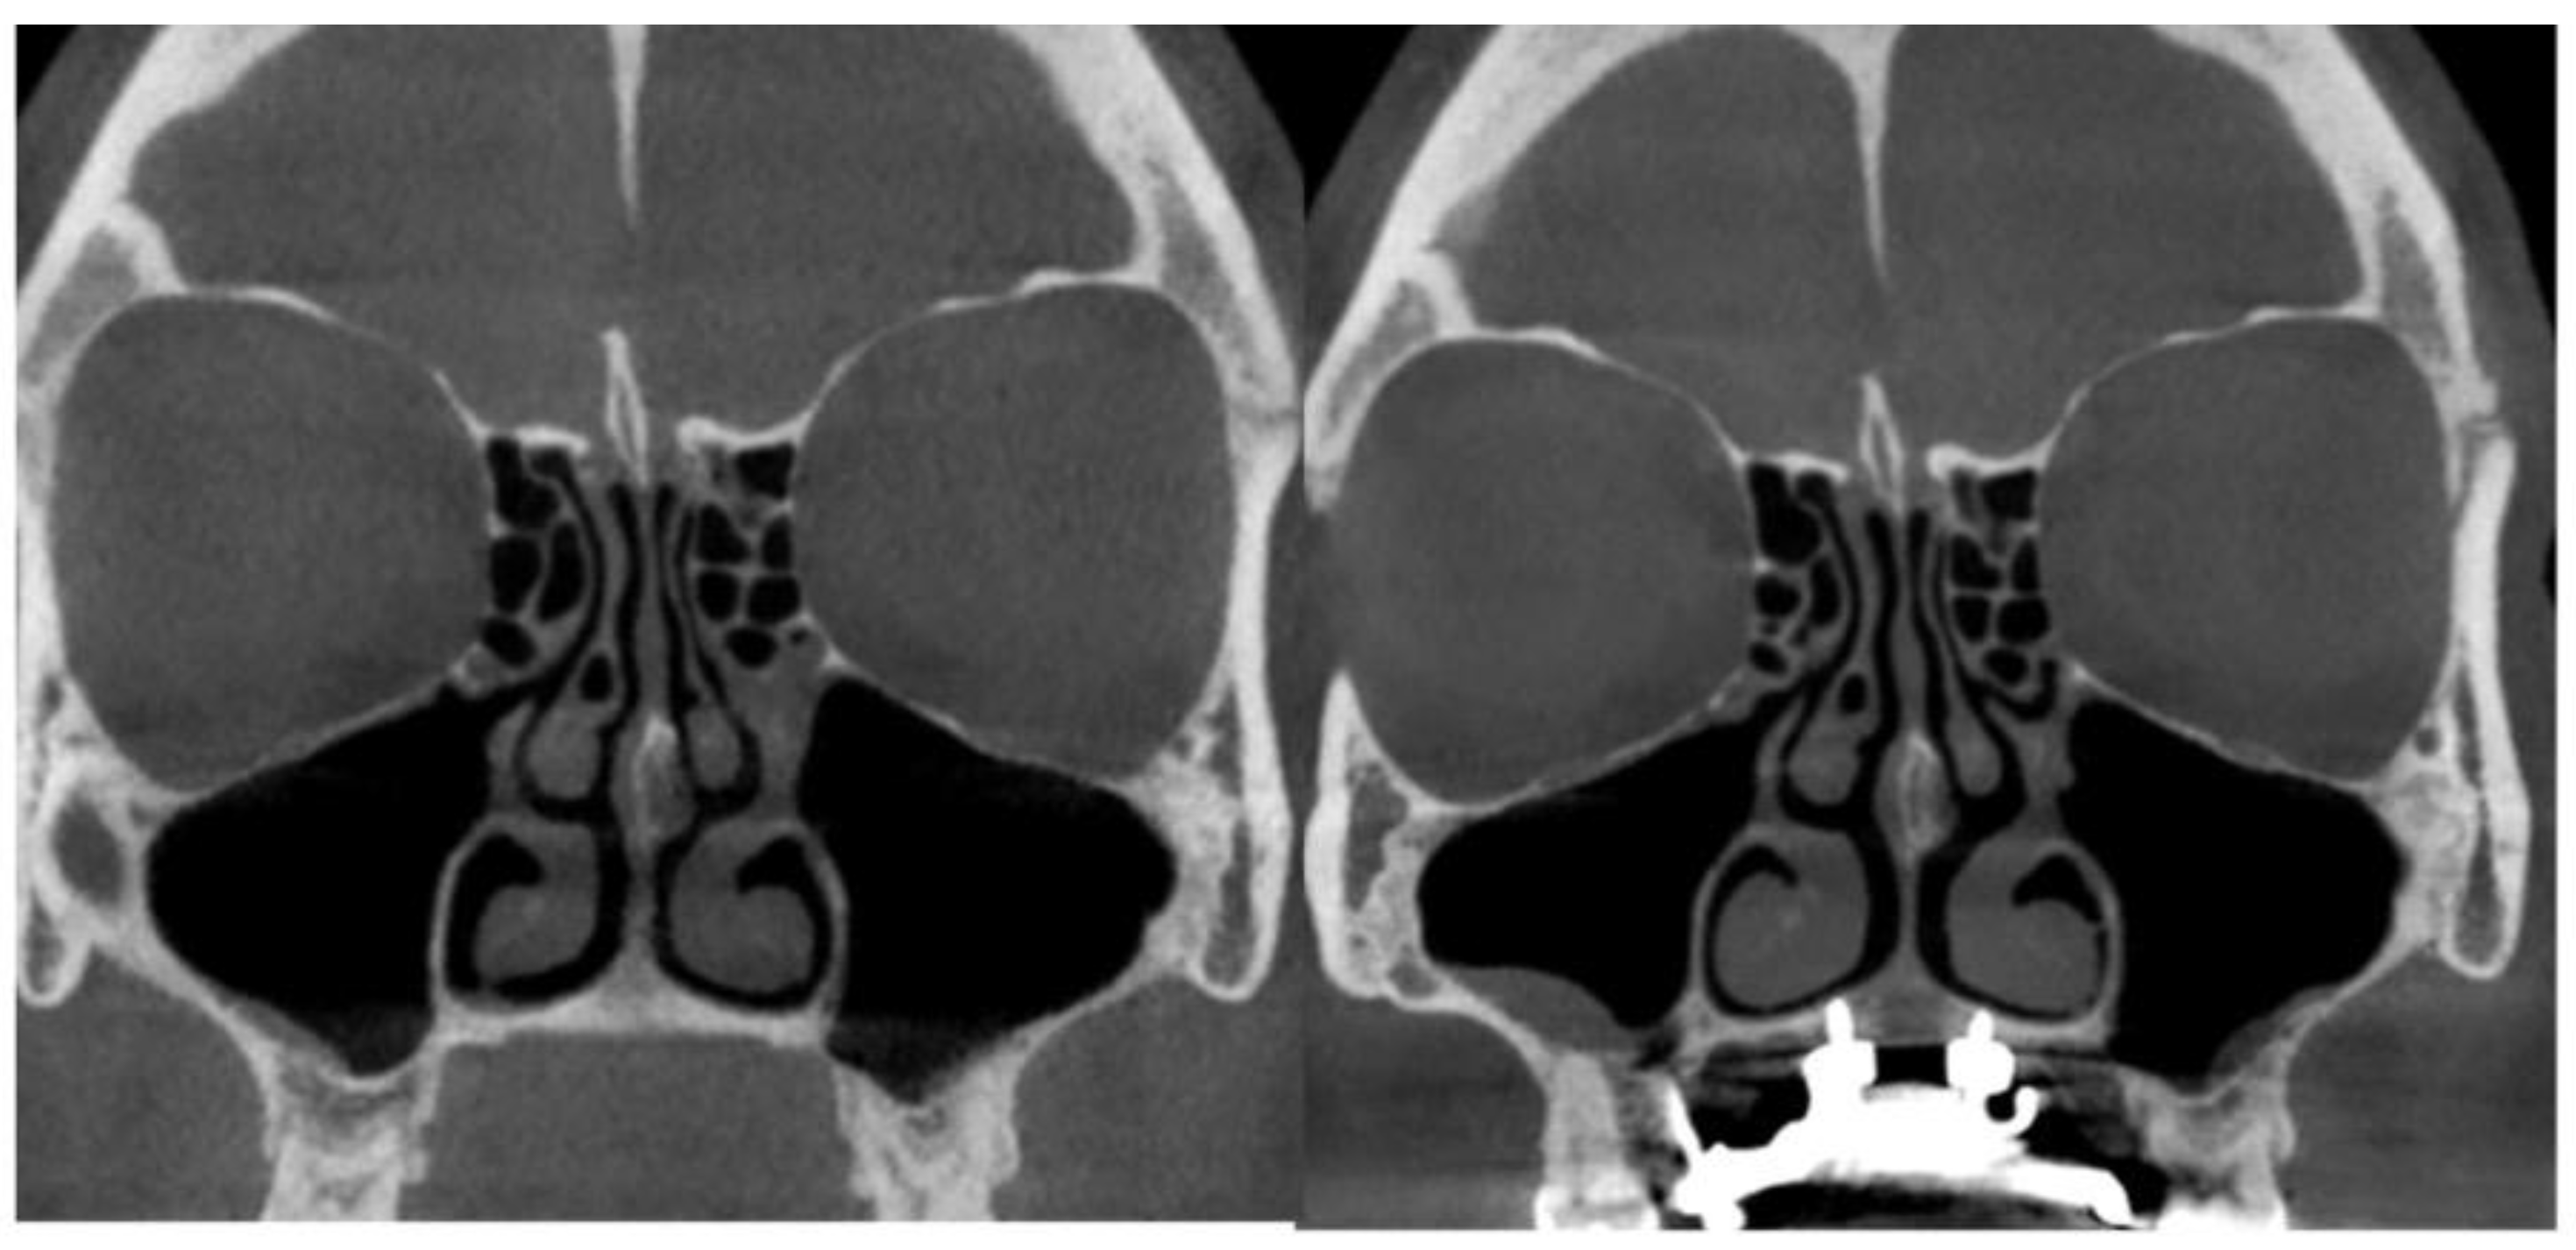

- Asymmetric expansion with residual attachment of the nasal septum unilaterally to the maxillary crestal bone (Figure 5,6);

- Diagonal fractures of the palatine bone extending from the distal margin of the palatal process of the maxillary bone unilaterally, often associated with pain and tension;

- Asymmetric displacement of the nasal base floor with unilateral downward and outward movement (Figure 5,6)

- Downward inclination and displacement of the alveolar process on the ipsilateral side (Figure 5,6);